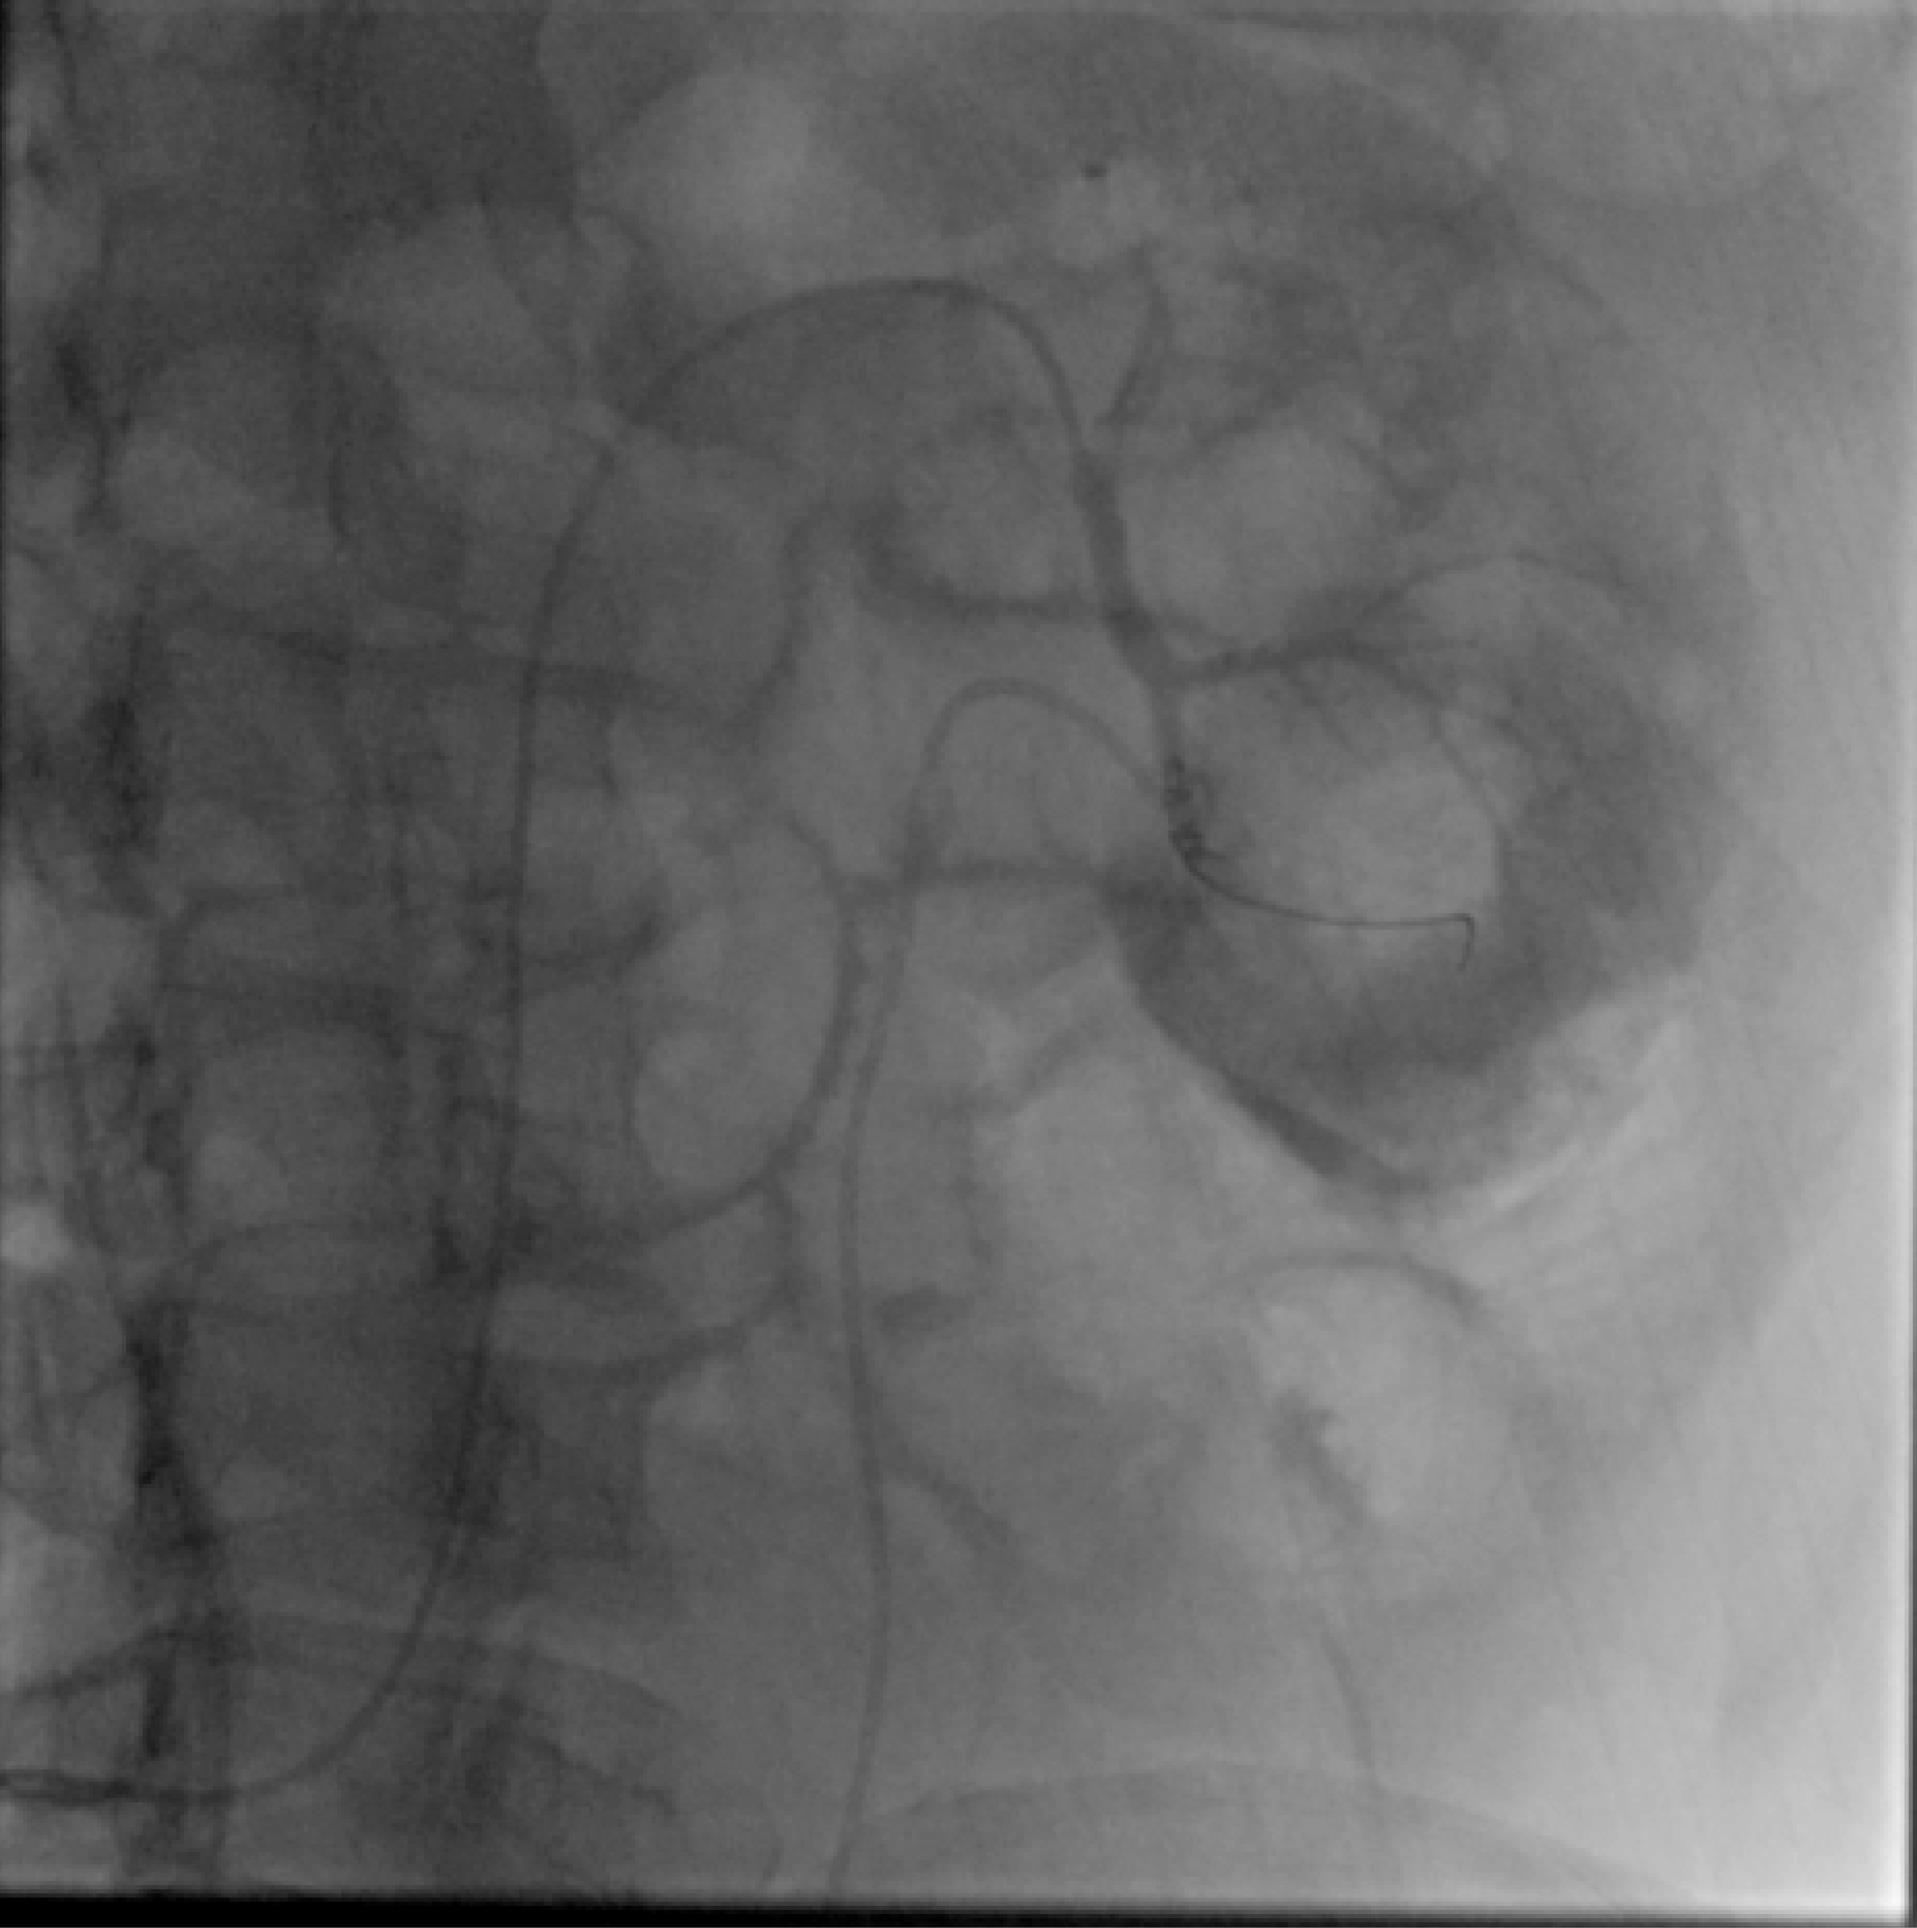

Figure 2.

Selective angiography showing a renal artery branch pseudoaneurysm

Angioembolization Technique

The access was from common femoral artery in 6 cases and it was from left brachial artery in one case by using 6 French (Fr) femoral or Radial sheath respectively. All cases were performed under local anesthesia. Angiography of aorta and renal arteries was performed by a Pigtail 5Fr catheter followed by road mapping. Visualization of a saccular shape contrast along the artery translated to pseudoaneurysm. Figure 2 Selective angiography of affected renal artery and branches were performed by Cobra, Vertebral and MP catheters. Then microcatheter (2.7 Fr) and 0.018 or 0.014 guidewires were used to reach the bleeding artery and passed into the pseudoaneurysm. Coil embolization was performed by MicroNester and MReye coils (Cook, Inc.). Size of coils was selected based on angiography results considering the size and volume of the pseudoaneurysm. Table 1 tabulates the procedural characteristics of the patients. Completion angiography revealed embolized pseudoaneurysm in all cases. Blush of contrast material was not seen in any of the cases. Figure 3 Gross and microscopic hematuria disappeared in all patients in the following days, which we defined as clinical success. These patients were monitored closely, and complete blood counts and renal function tests were performed daily until stabilization.